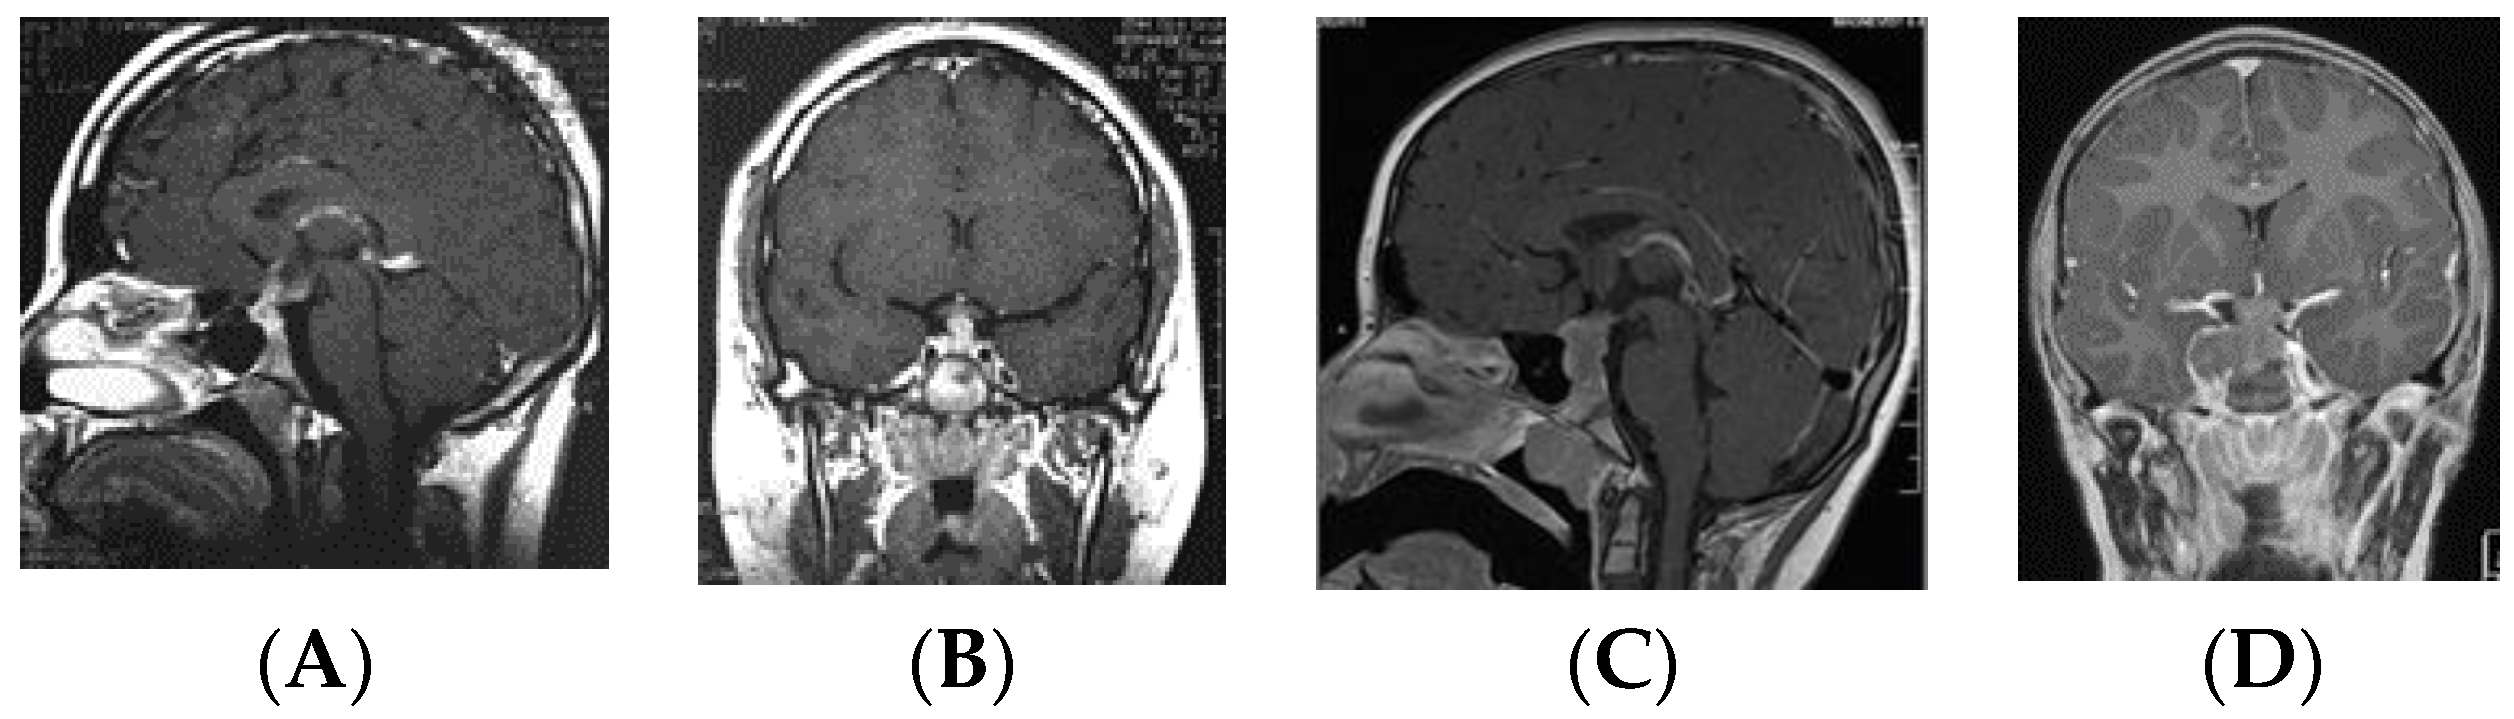

• Type Ia: Globular anterior III ventricle lesion with identifiable PS and PG (Figure 1);

Figure 1. Type Ia. Post-contrast MR, sagittal (A) and coronal (B) views of a patient with suprasellar germ cell tumor (S-GCT) and post-contrast MR, sagittal (C) and coronal (D) views of a patient with bifocal GCT. Note an anterior third ventricle tumor with preserved pituitary stalk and gland.